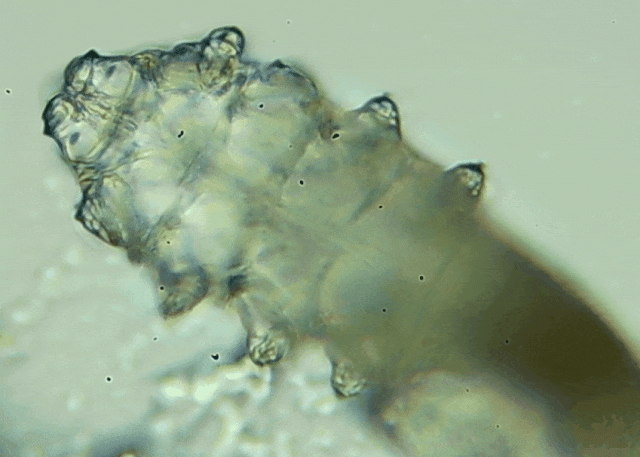

蠕形螨是一類肉眼看不見的寄生螨,常見的有毛囊蠕形螨和皮脂蠕形螨,常駐在人類的毛囊和皮脂腺里,尤其是眼睛的瞼板腺和睫毛根部。數(shù)量少時(shí),蠕形螨能與人體“和平共處”,但一旦你免疫力下降、油脂分泌旺盛或清潔不到位,他們就會(huì)以你難以想象的速度瘋狂繁殖。

而且這不是極端個(gè)案,廈門眼科中心干眼門診的臨床數(shù)據(jù)統(tǒng)計(jì),眼睛經(jīng)常紅癢發(fā)炎的人群,多數(shù)都有螨蟲,約80%以上的瞼緣炎患者螨蟲超標(biāo),一根睫毛最多能有幾十只。

當(dāng)螨蟲攻占眼部時(shí),通常會(huì)有這些癥狀,如反復(fù)發(fā)作的雙眼紅癢、干澀、燒灼感;分泌物增多,早起出現(xiàn)“眼屎拉絲”;睫毛容易掉,嚴(yán)重時(shí)出現(xiàn)倒睫或亂睫等;長期螨蟲感染還會(huì)誘發(fā)干眼、角膜炎,甚至視物模糊等。